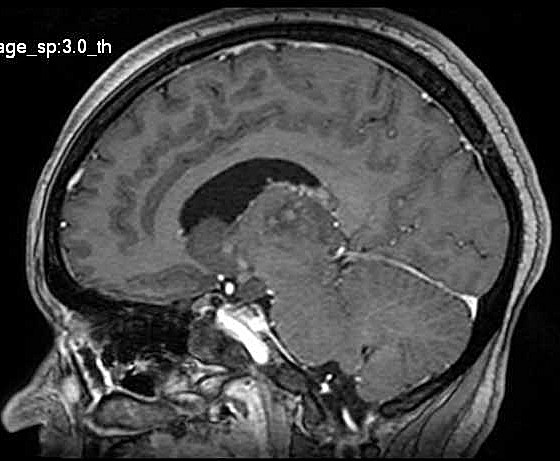

| Fem. 17a. |

| Nódulo sólido homogêneo preenchendo o III ventrículo, com limites precisos, com hipossinal em T1 e hipersinal em T2 e FLAIR, que se impregna por contraste paramagnético. Lesão menor implantada no assoalho do IV ventrículo provavelmente representa disseminação por via liquórica. |

| CORTES AXIAIS, T1 COM CONTRASTE | ||

| F. 17a. Tumor teratóide rabdóide atípico de III ventrículo. RM | HE | VIM, GFAP | HHF35, desmina, 1A4 | AE1AE3, EMA |